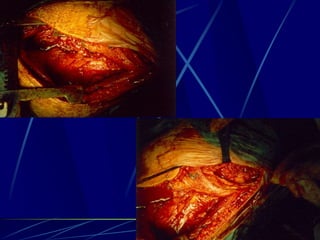

Infections of the spine

Φυματίωση της σπονδυλικής στήλης